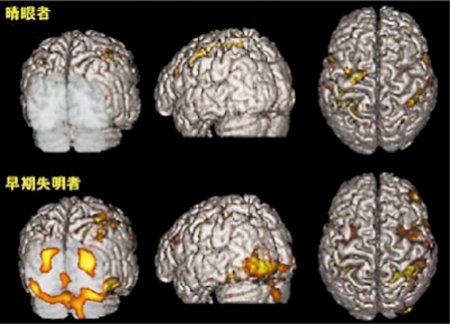

視覚障害者の点字弁別課題における両側一次視覚野の脳賦活

早期視覚障害者における右示指による点字弁別課題中の脳賦活状態を,高分解能MRlに重畳した(下段)。黄色く示した部位で,課題遂行中に統計的有意に血流が増加したことを示している。一方晴眼者(上段)では後頭葉の賦活は全く見られない。視覚障害者では,後頭葉への視覚情報入力が欠損しているにも関わらず,点字読を含む触覚課題によって一次視覚野に劇的な神経活動が生じていることがわかる。幼少時からの視覚脱失により脳の可塑性が発揮されたものと考えられる。